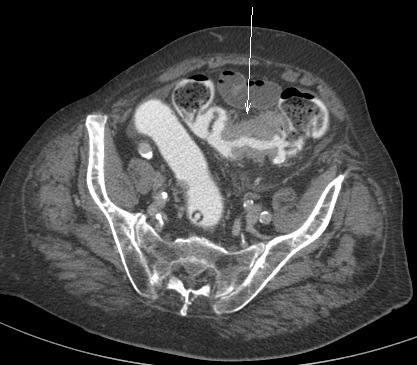

Patiente 75 ans sans atcd, avec douleurs abdominales aiguës , défense et sd occlusif du grêle. A la biologie RAS hormis sd inflammatoire. diagnostic?

Ischémie mésentérique artérielle